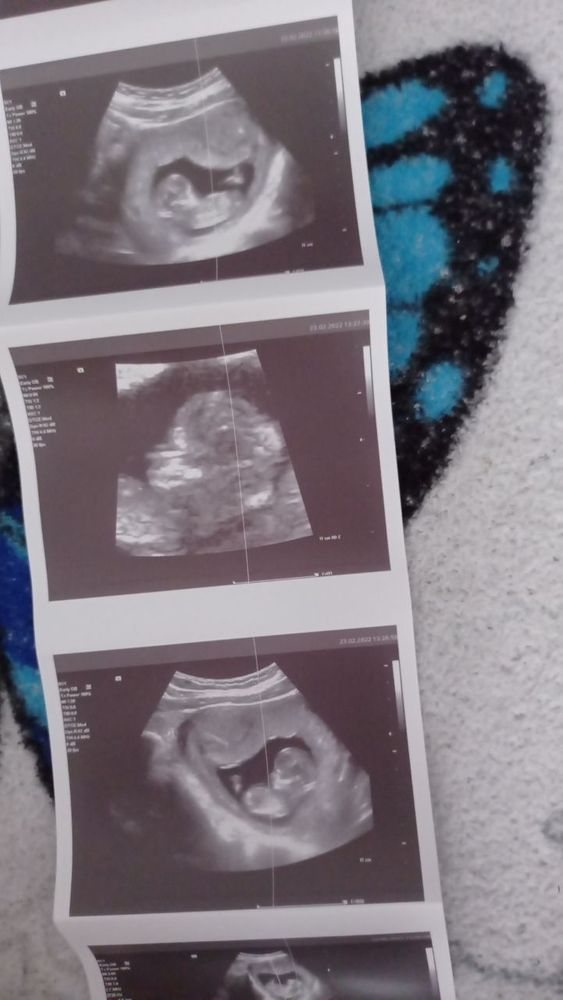

Пол ребёнка по узи, кто что видит?

Здравствуйте, видела тут девчонки на форуме, специалисты и видят по узи, нам уже 12 недель и 3 дня

Вижу девочку, но это не точно. Сейчас пока только предположить можно.